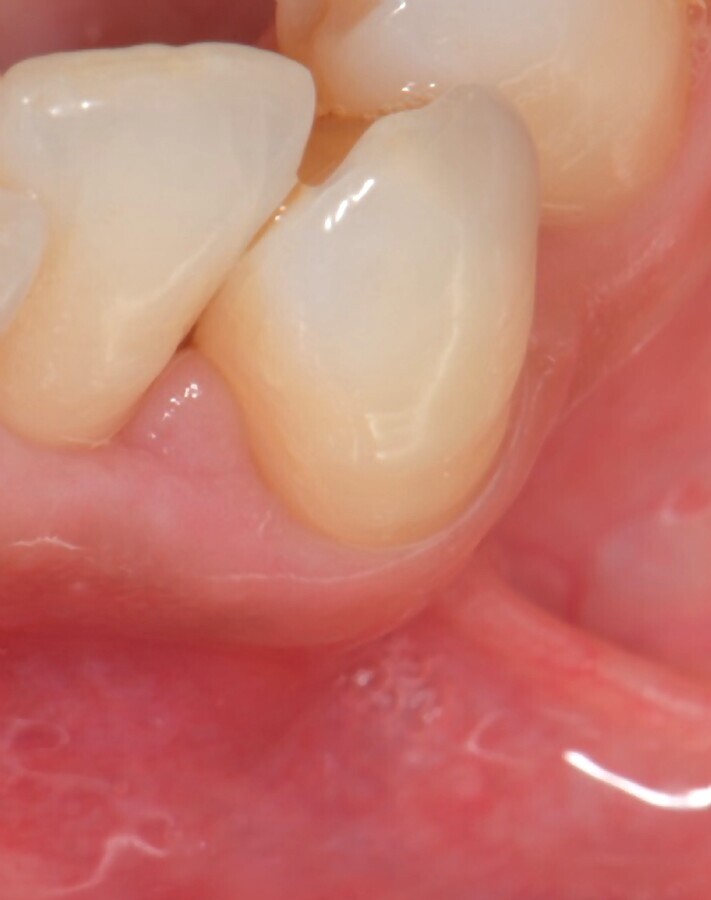

Figura 6. Vista oclusal del defecto tratado a los 7 días de seguimiento. Obsérvese la ausencia de inflamación y el tejido cicatrizado.